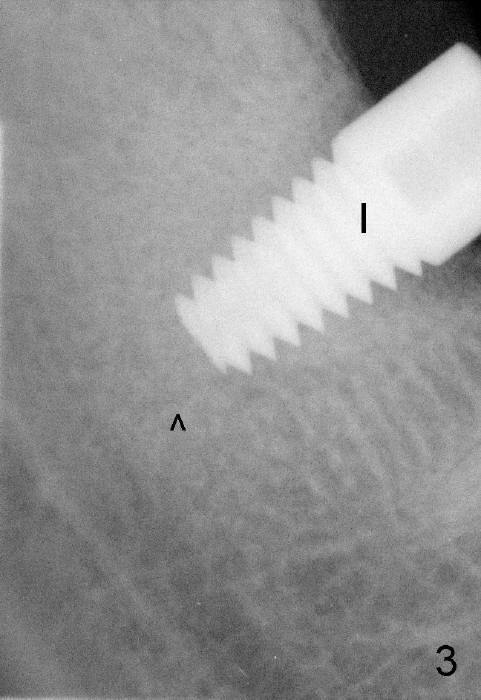

It is advantageous to place implant immediately or shortly (4-8 weeks) after extraction.  But most teeth to be extracted are potentially infected, such as in the case of Ms. Pei (Fig.1).  Periapical radiolucency (PARL) is not obvious prior to extraction. Six weeks post-extraction, osteotomy is finished with bone expansion and drilling (Fig.2 D, 5x14mm).  Tatum tapered implant is placed (Fig.3 I: 6x14). So far PARL is minimal if any (Fig.2,3 <).  Pain develops approximately 20 days post-implantation with expanding PARL (Fig.4 <).  Antibiotic treatment does not resolve the infection.  The implant has to be removed.  Infected granulation tissue is thoroughly removed from the apical portion of  the socket (Fig.5 <) with a curette (C).  Scaling and root planing is done for 4 quadrants.  A month later, potentially infected hard tissue is removed by reamers (Fig.6 D, 5 mm).  Bicon implant is buried inside the bone and separated from the oral cavity (Fig.7 I, 5x8).  At that time, there is a gap next to the implant (>).  Five months later, the gap disappears, suggesting implant osteointegration (Fig.8).  Extraoral cementation is done between abutment (A) and crown (C).  The abutment/crown unit is tapped into the implant with 2 visible threads (<).  The latter indicates that the abutment is completely seated.  Dashed lines in Fig.5-7 denote the upper border of the inferior alveolar canal.  PAs are taken 6 months (Fig.9) and 1 year 7 months (Fig.10) post cementation.  In all, it is a hassle to do re-implantation.  Efforts should be exerted to prevent post-implant infection.